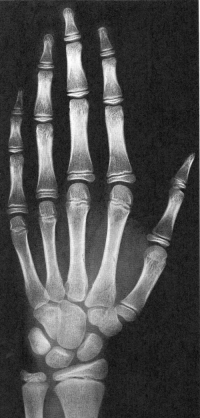

Sexo Feminino

14 anos

15 anos

16 anos

Fonte: GREULICH, W.W. & PYLE, S.I.: Radiografic Atlas of Development of the Hand and Wrist. Stanford University Press, 2° edition, 1959.